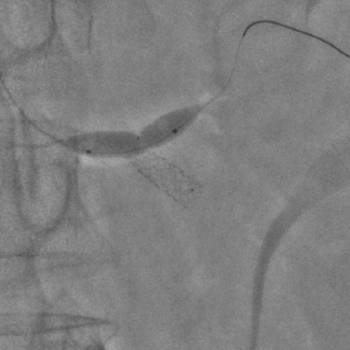

Бифуркационное стентирование почечной артерии

Ангиографическое исследование аорты и селективная ангиография сосудов почек выявило критический стеноз a. segmenti inferioris и короткую a. renalis sinistra

Операторы: Андрей Мальцев, Дмитрий Лебедев